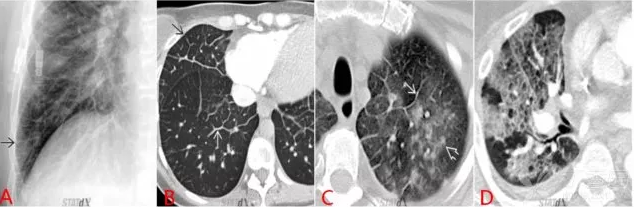

圖 1 心源性肺水腫典型表現(xiàn):肺紋理重新分布

圖 1A 為正常胸片,B 為一心衰患者胸片。圖 1B 為典型間質(zhì)性肺水腫表現(xiàn):肺上野和外帶肺紋理顯著增多,并可見 Kerley 線(細(xì)白箭指示)

圖 1D 患者為急性左心衰患者,與治療后癥狀緩解時相比(圖 1C),其近胸膜處肺紋理顯著增多,左肺可見彌漫性滲出,并可見雙側(cè)胸腔積液。